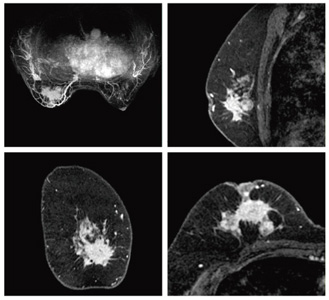

図3 VIBRANT(両側同時乳房撮像)(1.5T)

ボリュームデータとして取得した後,任意の断面にリフォーマットした例

(画像ご提供:北里大学病院様)